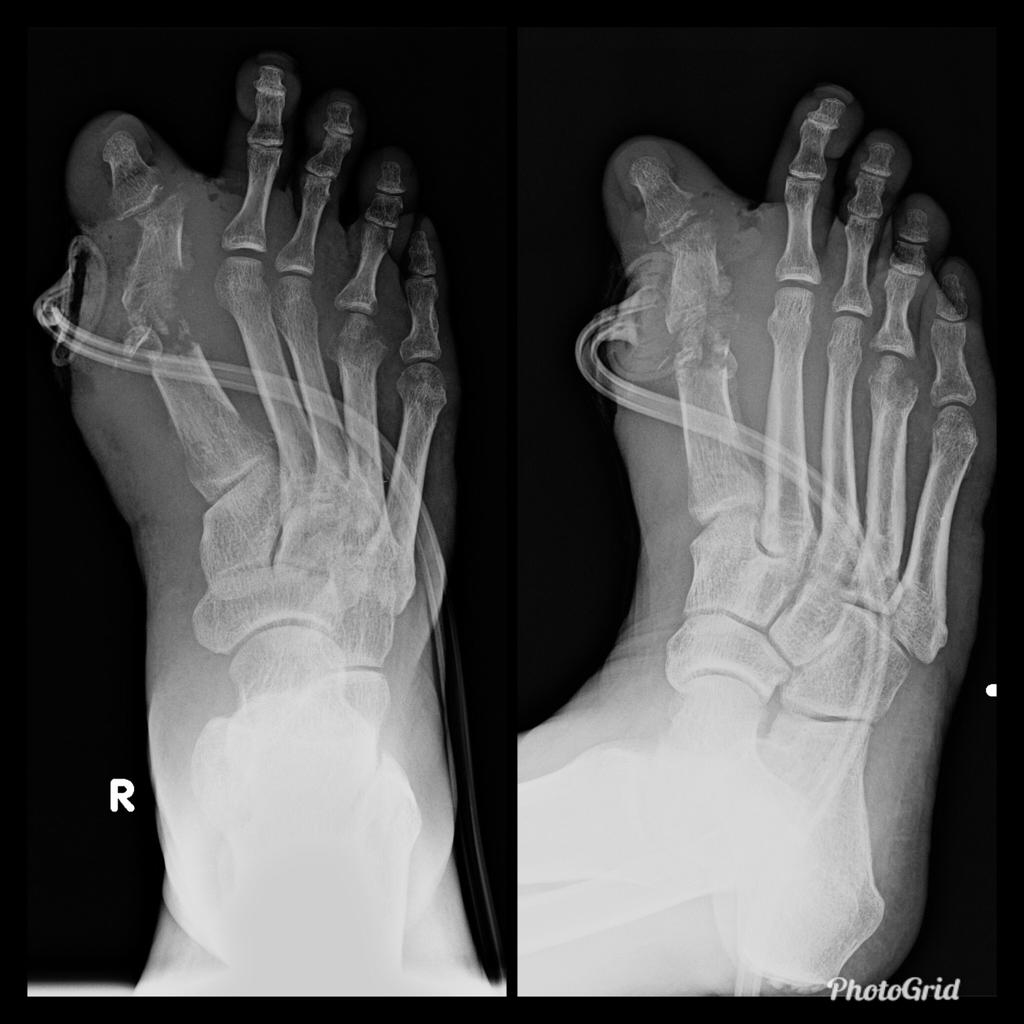

Osteomyelitis in diabetic foot is infection of the bone that 90% are results from contiguous spread of a skin ulcer. Consequently, the most common location for osteomyelitis is at the pressure points of the forefoot (metatarsal heads, IP joints) and in the hindfoot at the plantar aspect of the posterior calcaneus. Classic triad of osteomyelitis in plain radiograpy are lucencies, periosteal reaction, and bony destruction.

Unlike osteomyelitis, Charcot neuroarthropathy is primarily an articular disease and not related to overlying skin or soft tissue changes. Charcot neuroarthropathy commonly involves multiple midfoot bones. Features include joint instability, dislocation, destruction, disorganization, increased bone density, joint debris and deformity. Presence of subchondral cysts and intraarticular bodies with absence of the secondary signs for osteomyelitis support neuroarthropathy without infection.

In the early stage radiography will not demonstrate bone abnormalities, but MRI will show subchondral bone marrow edema. The subcutaneous soft tissues are not typically involved in Charcot arthropathy.

Osteomyelitis in chronic Charcot is usually located in the midfoot, while osteomyelitis in diabetic neuropathy without Charcot is usually in the forefoot and hindfoot.

Diabetic foot remains a challenge for the clinicians due to confusing clinical picture and associated complications. It may present as neuroarthropathy, septic arthritis, osteomyelitis, ischemic devitalised bone or as soft tissue complications such as cellulitis, myositis, ulceration, callus formation, sinus tracts, abscess, muscle denervation, tenosynovitis etc. Awareness of the various imaging findings of a diabetic foot, their relevance to the therapeutic decisions and correct usage of various imaging modalities to answer pertinent clinical questions are very important to improve the patient management and to reduce complications and morbidity.

Plain radiography is the preferred first line imaging investigation. It can show osseous structures and joint spaces well however it is neither sensitive nor specific. The detection rate and accuracy is low, especially in the scenario of early infection or neuroarthropathy, due to its lack of adequate demonstration of the soft tissues. In addition, Charcot’s foot and osteomyelitis may show overlapping radiographic features.